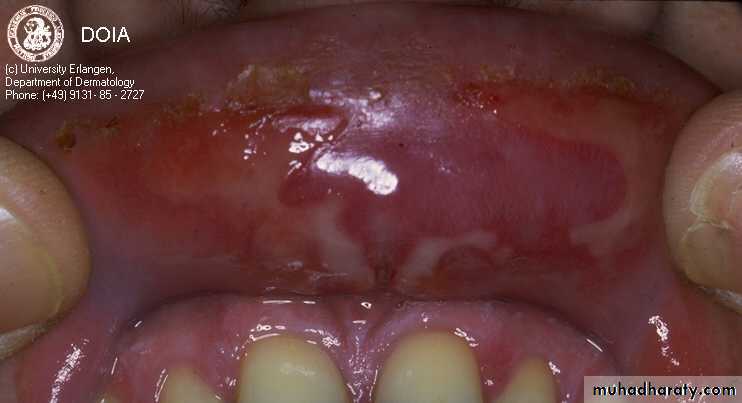

Mucous membranes of the mouth, pharynx and larynx may be involved and cause painful oral erosions, dysphagia and hoarseness of the voice respectively. Oral lesions (Painful erosions and ulcerations) are the presenting feature in about 50% of the patient and oral involvement occurs in almost all patients during the whole course of the disease.

Upper lip

Lower lipInner Cheek

Tongue

PV of the oral mucous membranes